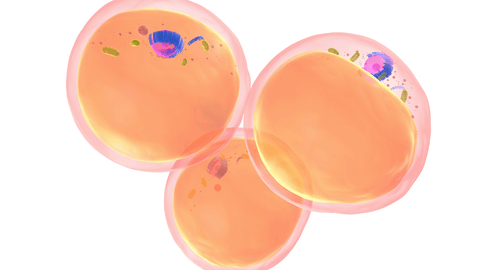

World-first gene therapy clinical trial for type 1 diabetes to proceed

A world-first clinical trial developed by Garvan researchers was launched to test how genetically engineered cells might restore insulin function and reduce the need for immunosuppression in patients with type 1 diabetes. In the trial, pancreatic islet cell that have been genetically engineered to prevent the immune system from damaging them, are transplanted into the livers of participating patients. Islet cells are responsible for sensing the concentration of sugar in the blood and producing the hormone insulin. If successful, this new therapy will eliminate the need for patients to take immunosuppressants, while also reducing a patient’s reliance on insulin injections.